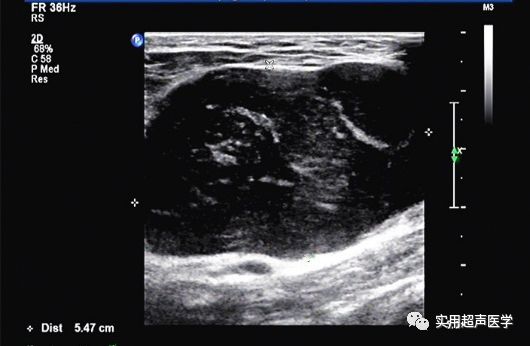

超声检查:右腋下肿块处扫查,皮下软组织内探及55×34mm低回声,边界清,浅分叶,内部回声欠均匀,内可见散在条状高回声分布,CDFI示其内较丰富的短线样血流信号,阻力指数(RI)0.37。超声提示:右腋下实性团块(性质待定,建议活检穿刺)。

超声图像主要表现为以下几点:1、肿块呈单发低回声,边界清楚,多数可显示细亮包膜回声;2、内部回声常欠均匀,内部可见片状、点状高回声,也可出现伴声影的钙化灶;3、彩色多普勒血流显像(CDFI)显示其内部血供较丰富,可呈多发散在短棒样血流信号,部分血供极丰富的病例,亦可呈甲亢样“火海征”表现,(与小血管增生的病理表现相符合);4、脉冲多普勒(PW)测得肿瘤内部低速低阻型动脉血供,阻力指数(RI)多小于0.4。

发生于颈部和腋下的局限型Castleman病在超声上表现为单发肿块,边界清,有包膜,内部多为不均匀低回声,常伴有条状和(或)点状的强回声,CDFI示其内丰富血流信号,呈短棒状散在分布,PW测得瘤内动脉频谱为低速低阻型。临床上如发现无症状的单一淋巴结肿大,超声有上述表现的,应怀疑此病并与类似病变相鉴别。结合患者病史和查体可提高诊断符合率,而确诊需行穿刺或手术病理活检。